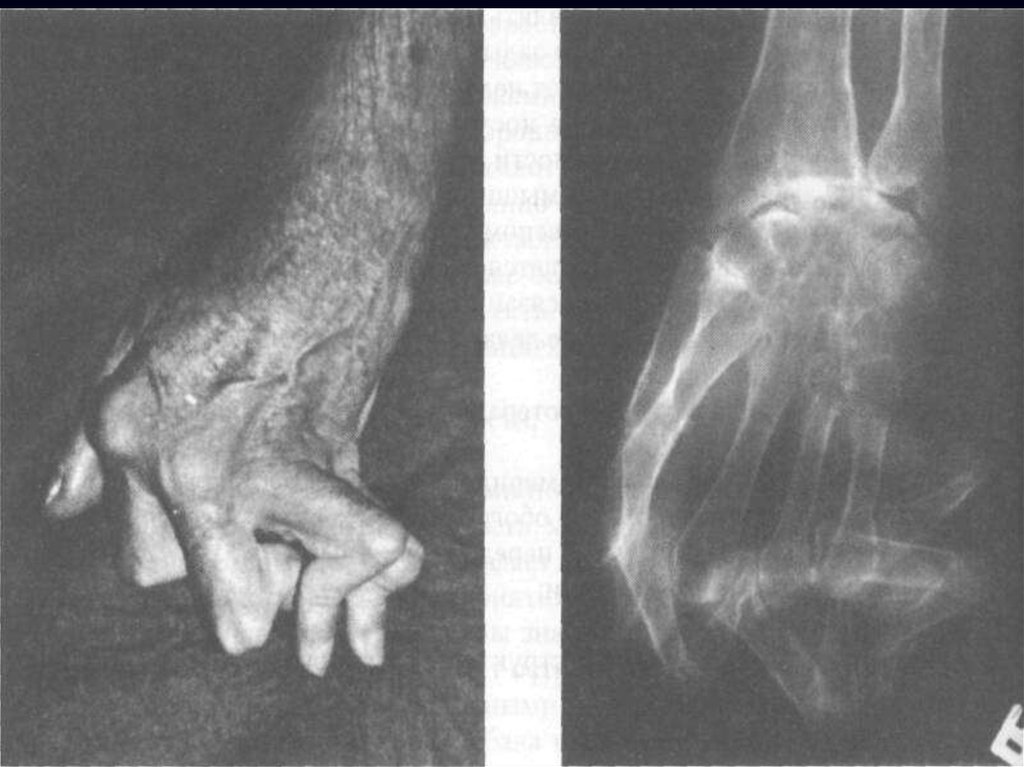

Характеризуется симметричным хроническим эрозивным

артритом (синовитом) периферических суставов и

Необратимые структурные –

эрозии, анкилоз

Предотвращение деструкции, нарушения

функции и деформации суставов